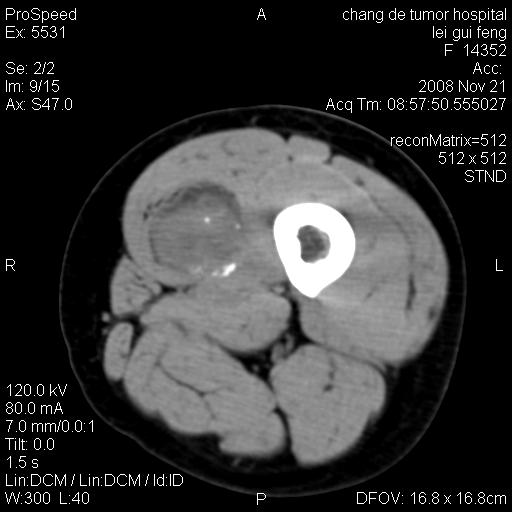

标题: CT16807:女 41 无不适 [打印本页]

标题: CT16807:女 41 无不适

考虑皮样囊肿可能性大

血管瘤可能

血管瘤

血管瘤可能性大!

黏液瘤或表皮杨囊肿

不排除横纹肌肉瘤可能。

血管瘤可能性大或畸胎瘤

考虑脂肪肉瘤

考虑血管瘤可能性大;不排除肉瘤可能。建议行活检。

脂肪肉瘤?

双是软组织肿瘤,病灶内多发钙化,另可见多量脂肪密度影,考虑畸胎瘤,血管瘤,不除外其他